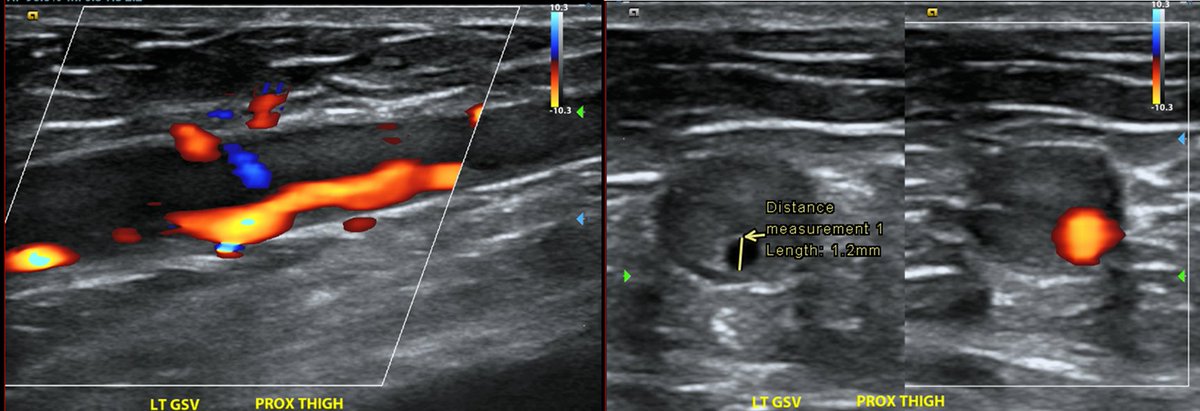

Venous insufficiency US shows an arterial structure "inside" the GSV. Diagnosis? @SIRspecialists

Michael Cumming tweet media